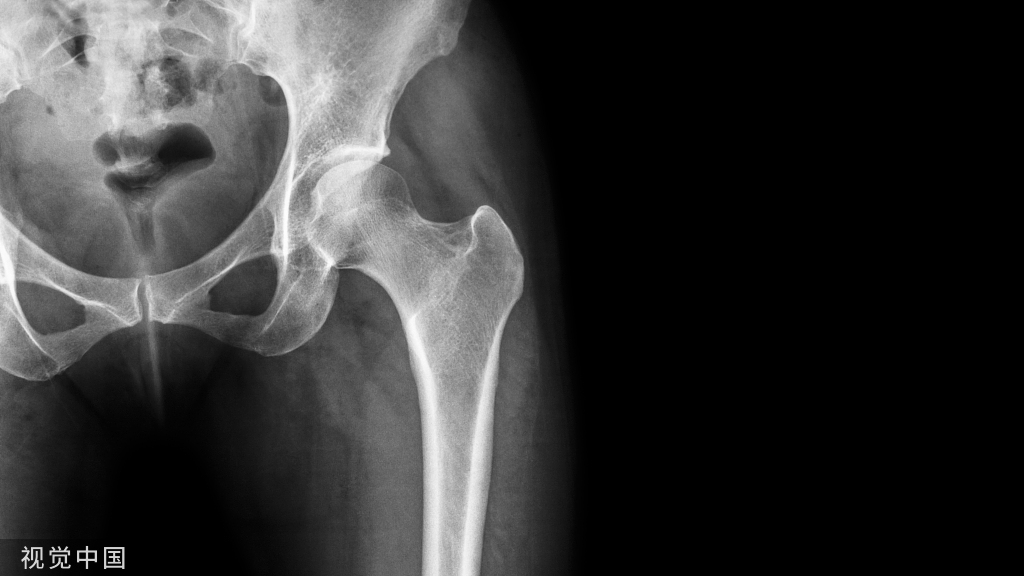

掌侧锁定接骨板固定是桡骨远端关节外骨折最常用方法,桡骨远端骨折目的是恢复掌倾角、尺偏角及桡骨高度,通过利用解剖钢板的解剖弧度,先固定远折端骨块后借助钢板复位,已被众多研究者证实为可靠的方法。

掌侧锁定接骨板固定是桡骨远端关节外骨折最常用方法,桡骨远端骨折目的是恢复掌倾角、尺偏角及桡骨高度,通过利用解剖钢板的解剖弧度,先固定远折端骨块后借助钢板复位,已被众多研究者证实为可靠的方法。但该技术存在的一个难点为如何将钢板置入在准确位置,因钢板位置偏差可能导致重复复位置钉的风险。因此有学者使用了一种新的钢板定位方法,取得良好效果,结果发表在近期Injury上。

掌侧钢板是治疗桡骨远端背侧移位关节外骨折最常用的手术方法之一。然而,恢复掌倾角有时间是困难的。其通常需要进行手腕屈曲动作,同时保持、拧紧钢板,过程比较繁琐

而钢板定位也是其中一个关键的步骤,由于钢板的尺寸相对于桡骨远端的宽度很大,其定位也有时较为困难。

我们在复位前置入远端所有螺钉,然后我们利用锁定板的解剖形状,通过用皮质加压螺钉将桡骨近端固定到钢板上减少背倾。为了确保板的方便、准确定位,我们以徒手方式在分水岭线近端10毫米和距掌侧骨皮质内侧缘外侧10毫米处钻一个导向孔,而不定位板。这样可以清楚地看到导向孔的位置。然后在单皮质非锁定螺钉的帮助下将锁定板固定于桡骨远端,并且在透视下对其进行控制。当导向孔被正确定位并且板在前后方向上位置良好时,剩余的远端螺钉孔置入锁定螺钉。然后用双皮质加压螺钉将钢板固定在桡骨近端,从而减少桡骨背倾。我们认为这种技术是一种安全和可重复的方法来定位掌侧钢板,并在解剖学上减少关节外移位桡骨远端骨折(AO A2和A3)的背倾。此外,该技术提供的骨折制动复位减少了手术时间和辐射。